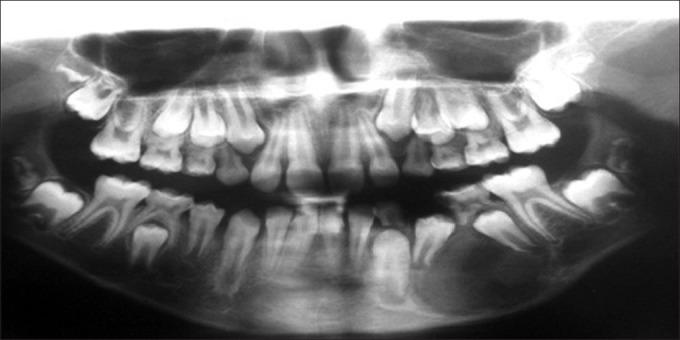

Intraosseous schwannomas is a very rare neoplasm, and less than 50 cases have been reported in the medical literature. In this article, the clinical, radiographic and histopathologic appearances of a rare case of intraosseous schwannomas are presented. The importance of this case is that other benign central lesions such as odontogenic tumors and cysts might be included in differential diagnosis. This case was recognized in a 9-year-old child, which is a very rare occurrence. The diagnosis was confirmed by immunohistochemical staining with S100 protein.

骨内施万细胞瘤是一种非常罕见的肿瘤,医学文献中报道的病例不足50例。本文介绍了一例罕见的骨内施万细胞瘤的临床、影像学和组织病理学表现。该病例的重要性在于,在鉴别诊断中可能需要考虑其他良性中心性病变,如牙源性肿瘤和囊肿。该病例发生在一名9岁儿童身上,极为罕见。通过S100蛋白免疫组化染色确诊。